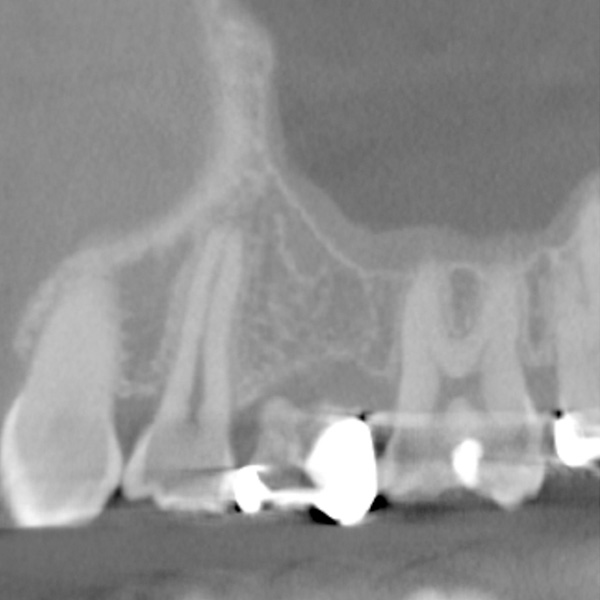

| 年代・性別 | 50代 男性 |

|---|---|

| 主訴 | 右下の歯がないのでインプラントをして欲しい |

| 治療期間 | 約6ヶ月 |

| 費用 | 600,000円 |

| 治療内容 | インプラント、骨造成、結合組織移植、セラミック修復 |

| 治療に伴うリスク | インプラント周囲炎 セラミックの破折、脱離 |

*キャンセルポリシーをご一読のうえご予約ください